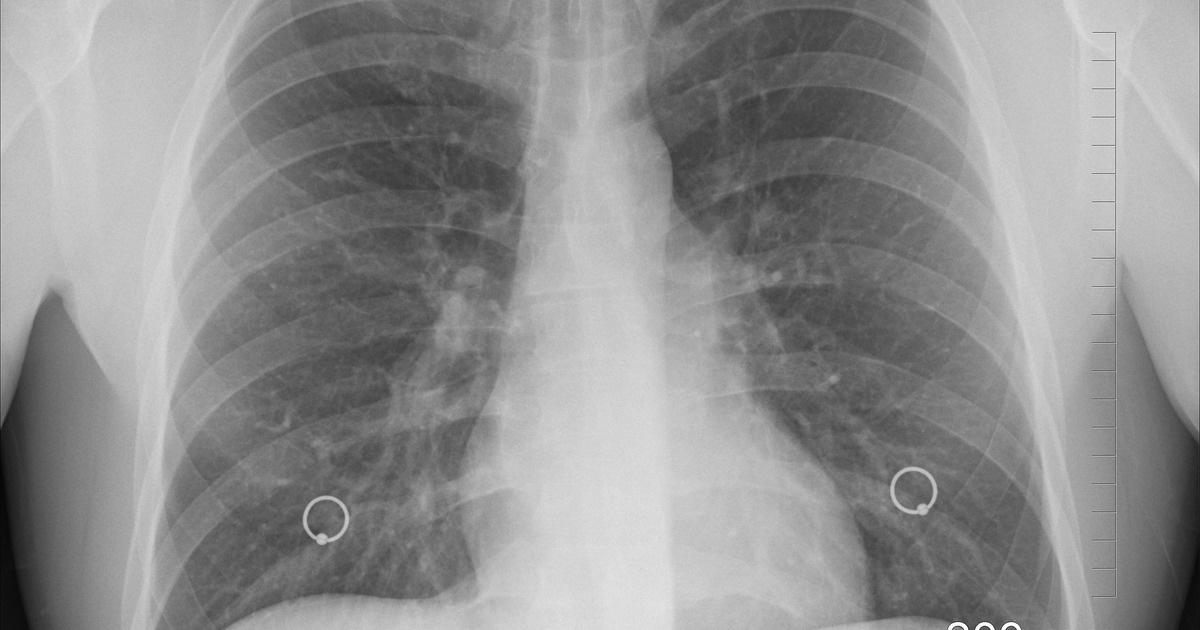

Фото с сайта pixabay.com